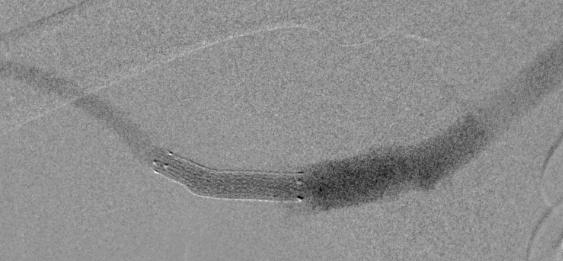

Why 25 years of patient-centered innovation really matters

One mainstay endovascular aneurysm repair (EVAR) device is celebrating not just a quarter century of being commercially available, but the innovation it has inspired along the way. Michel Makaroun, MD, and Willy Davison, PhD, discuss the evolution and innovation of the GORE® EXCLUDER® device family over time.

Twenty-five years of patient impact and durability is worth celebrating in the life of any medical device. And when a device reaches this milestone, it is celebrating more than just 25 years in the treatment landscape. It is a legacy of making a difference for physicians and their patients.

The GORE ® EXCLUDER ® AAA Endoprosthesis for abdominal aortic aneurysm (AAA) is commemorating 25 years of commercial availability since earning its CE mark in September 1997. It has been used to treat more than 440,000 patients worldwide* and has become the most-studied EVAR device according to company-sponsored trials and registries shown on ClinicalTrials.gov for currently available stent grafts.

“The EXCLUDER® AAA Endoprosthesis has been on the market helping patients for well over two decades: A truly remarkable accomplishment and the longest stretch in the industry,” said Makaroun, chief of the Division of Vascular Surgery at the University of Pittsburgh Medical Center and an investigator in each EXCLUDER® device clinical study.

“The close collaboration between medical community and manufacturer has allowed for numerous innovations and improvements along the way, providing for more accurate deployment and better outcomes.”

“As EVAR became more prevalent and additional patient needs were uncovered, it was important that W. L. Gore & Associates—the global materials science company behind the device—continue exploring and improving EVAR solutions,” said Davison, Abdominal Aortic Global Business leader at Gore.

“We recognized the broader potential of the device but knew that there was still a need to keep improving, keep innovating, to help address even more patients’ unique needs and anatomies.”

Over the next two decades, Gore developed and studied additional solutions within its EVAR portfolio, receiving approvals for larger trunk and contralateral limb diameters, an iliac branch device, and a next generation of the EXCLUDER® device that is conformable and offers optional angulation control—allowing physicians more treatment options to consider for their patient’s anatomy.

Pre-implant

Davison said that at Gore, collaboration with the medical community is key to developing solutions that continue to advance patient care. “We are immensely grateful to the physicians who have put their trust in our devices to help their patients maintain their quality of life and those who have partnered with us as we continue exploring future solutions for AAA patients,” he said.

For more information on the GORE® EXCLUDER® AAA Endoprosthesis and the GORE® EXCLUDER® device family, scan the above QR code.

2004

EXCLUDER® device design features a nitinol stent, sutureless stent-to-graft attachment and proprietary ePTFE film layers

Four-year follow-up showing aortoiliac aneurysms treated with bilateral iliac branch devices